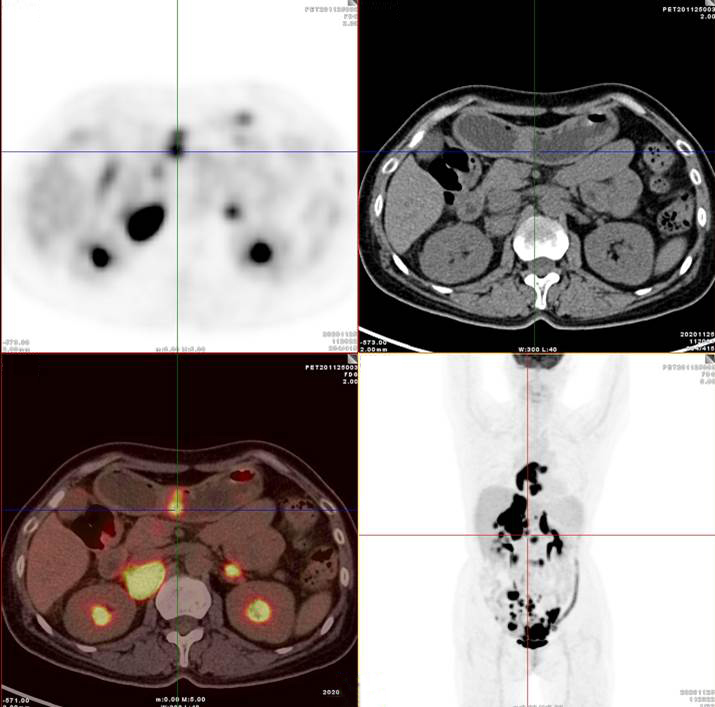

PET/CT影像圖

雙側(cè)腎上腺病灶、腹膜后淋巴結(jié)放射性攝取明顯增高

膽囊及雙腎上腺病灶、腹膜后淋巴結(jié)放射性攝取明顯增高

胃、雙腎上腺病灶、腹膜后淋巴結(jié)放射性攝取明顯增高